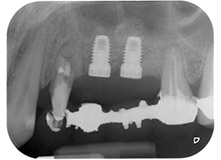

Finally, after periosteal incision, the site was passively sutured with a coronally advanced flap, using 5-0 absorbable suture material (Fig. 15). The postoperative radiograph showed both implants in their correct vertical position (Fig. 16).

Postoperative radiograph

Fig. 16: Postoperative radiograph showing the implants in place, with bone substitute material from the internal sinus lift around the apices. There is some material from the GTR procedure visible around the roots of tooth 24.